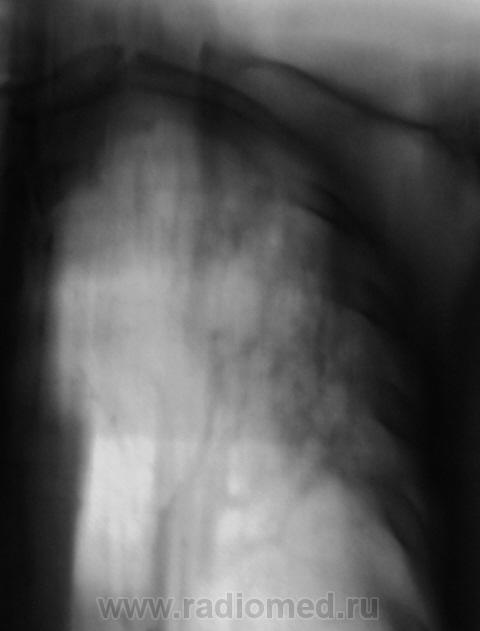

Вот, и мы так решили, с учетов ограничеснных возможностей нашей ЦРБ-ушки. Взял коллега фтизиатр "изображения", а также и изображения в динамике, а также необходимый "гарнир", и поехал в головное "фтизное" учреждение. В учреждении проконсультировали и выставили правосторонний инфильтративный. Ну и у нас считай - гора с плеч...

Пациента госпитализировали в областное противотуберкулёзное учреждение. Пролечили в течение месяца.... и выписали.

Произведен контроль после лечения. Заключение рентгенолога данного учреждения - "Со стороны органов грудной полости патологических изменений не выявлено".